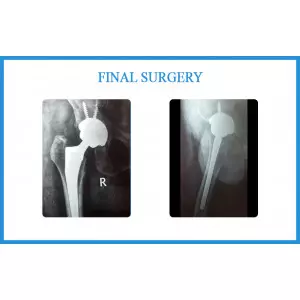

Categoryhip replacement surgery

Coxa Vara

A young girl aged 15 years had coxa vara and tuberculosis of right hip before 5 years. She had significant limping while... Continue